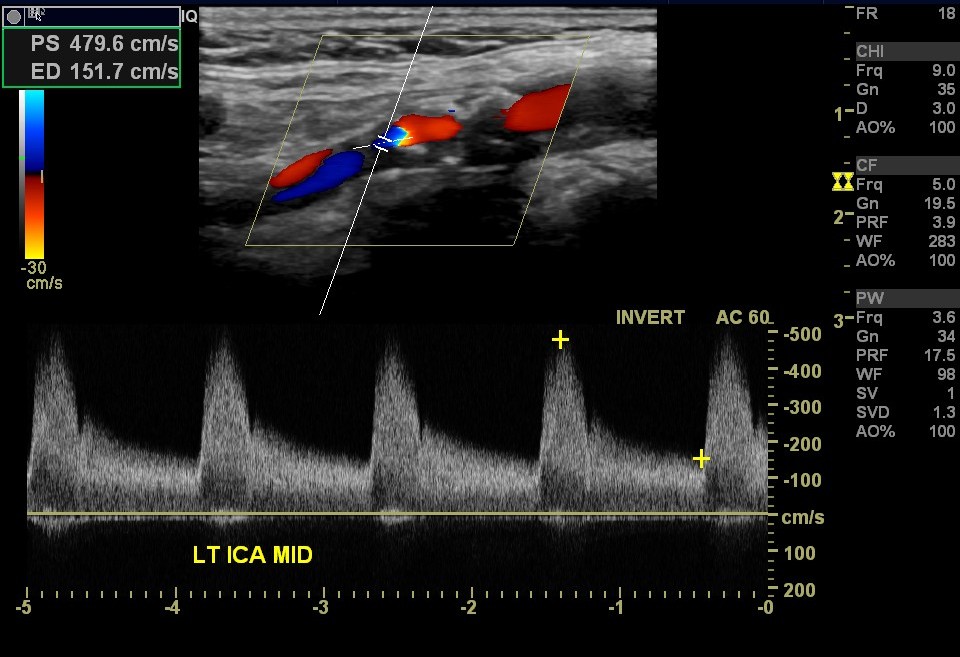

يُعتبر تضيّق الشرايين المغذيّة للدماغ من الأسباب الرئيسية للسكتات الدماغيّة، إلى جانب الصمُات الناتجة عن الرجفان الأذيني والاعتلال الأوعية الدقيقة. |

تؤدي الترسبات في الشرايين السباتية إلى تضيّق، وإذا ما انفصلت أجزاء من الترسبات والعصائد لتصل إلى الدماغ وتسد الأوعية الدماغية مُسببةً سكتة دماغية. وتُعزى 30 ألف حالة من أصل 200 ألف سكتة دماغيّة إقفارية إلى تضيّق الشريان السباتي حسب الدلائل الإرشاديّة الألمانيّة المصدرة في عام 2020. |

ويعاني الكثيرون من تضيق الشريان السباتي دون أعراض، وغالبًا ما يتم اكتشاف التضيق صدفة خلال الفحص الدوري عند طبيب الأسرة، طبيب الأعصاب أو طبيب القلب. وحتى الآن لم يوجد حل أمثل لمعضلة تضيق الشريان السباتي "الصامت"، أي الذي لم يُسبب أعراضًا بعد. واختلفت المدارس في توجيهاتها بين المدرسة المحافظة والتي تسعى لتقليل عوامل الخطر الوعائية كتنظيم ارتفاع الضغط الشرياني ومعالجة مرض السكري وتخفيض نسبة الدهون في الدم، بالإضافة إلى الابتعاد عن التدخين وتناول مثبطات الصفائح الدموية. |

أما المدرسة التداخلية فاختلفت بين التداخل الجراحي الوعائي (CEA)لإزالة العصائد الشريانية وبين التداخل الوعائي لوضع الداعمة في الشريان السباتي الداخلي (CAS). |

وحسب دراسة نُشرت في دورية NEJM قارنت دراستين شملتا 1245مريضًا من تضيق الشريان السباتي اللاعرضي في 155 مركزًا طبيًا في خمسة بلدن. وقارنت الدراسة الأولى، دراسة الدعامة (CAS) بين التداخل الوعائي والعلاج الدوائي، بينما قارنت دراسة التداخل الجراحي الوعائي بين الجراحة والعلاج الدوائي. |

كانت النقطة النهائية الأولية عبارة عن مزيج من السكتة الدماغية أو الوفاة، تم تقييمها في اليوم 44 بعد التوزيع العشوائي أو حدوث سكتة دماغية إقفارية من نفس جانب الشريان خلال أربعة سنوات بعد بدء الدراسة. |

في دراسة الدعامة وصل نحو 6٪من المشاركين في مجموعة العلاج الدوائي للنقطة الأولية، مقارنة ب 2,8٪ فقط من مجموعة التداخل الوعائي. أما في دراسة التداخل الجراحي فوصل 3,7٪ من مجموعة العلاج الجراحي للنقطة الأولية مقارنة ب5,3٪ من مجموعة العلاج الدوائي. |

وهكذا خلصت الدراسة إلى أن الجراحة لم تتفوق بشكل كبير على العلاج الدوائي مقارنة بالعلاج الوعائي. أما حسب دراسات المقارنة بين الطريقتين التداخليتين في حالة التضيق العرضي للشريان السباتي، فإن الجراحة والعلاج الوعائي بالدعامة متساويان، ويجب الاعتماد على الخبرات في المركز لتقرير استخدام إحدى الطريقتين. |